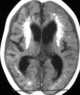

Cockayne syndrome (CS), also called Neill-Dingwall syndrome, is a rare and fatal autosomal recessive neurodegenerative disorder characterized by growth failure, impaired development of the nervous system, abnormal sensitivity to sunlight (photosensitivity), eye disorders and premature aging. Failure to thrive and neurological disorders are criteria for diagnosis, while photosensitivity, hearing loss, eye abnormalities, and cavities are other very common features. [Source: Wikipedia ]

Intracranial calcification

Leukodystrophy / leukoencephalopathy

Multiple intracranial calcification